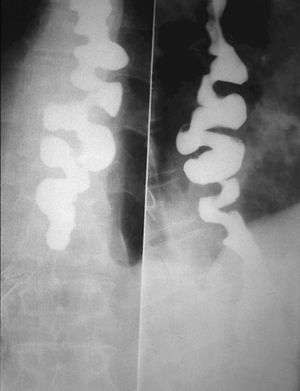

Several radiographic findings are suggestive of DES, such as a "rosary bead esophagus" or "corkscrew" appearance on barium swallow x-ray, although these findings are not unique to DES.[1]